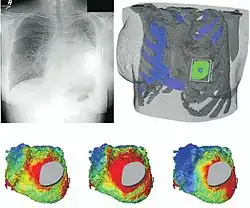

Patient-specific modeling in a patient with congenital heart disease.

Patient-specific modeling in a patient with congenital heart disease. -